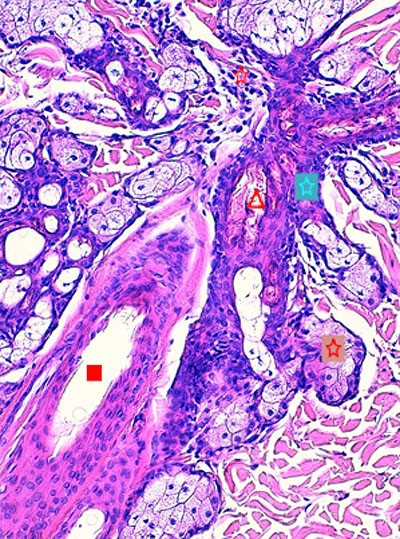

Photo 3 : (Hémalun Eosine X 100) : L’épiderme et les infundibula folliculaires montrent

une hyperkératose orthokératosique discrète à modérée, les canaux sébacés et les glandes sébacées

sont hyperplasiques, les glandes sudorales épitrichiales sont rétentionnelles et kystiques.

Légendes de la Photo 3 :

- Pointe de flèche rouge = hyperkératose orthokératosique de l’épiderme

- Étoile turquoise = derme périannexiel non inflammatoire hormis en zone péri-isthmique

- Étoile rouge = glandes sébacées plurilobulées hyperplasiques

- Carré rouge = portions infundibulaires et isthmiques des follicules pileux : la gaine épithéliale folliculaire externe est hyperplasique

- Étoile noire = lumière kystique des glandes sudorales épitrichiales